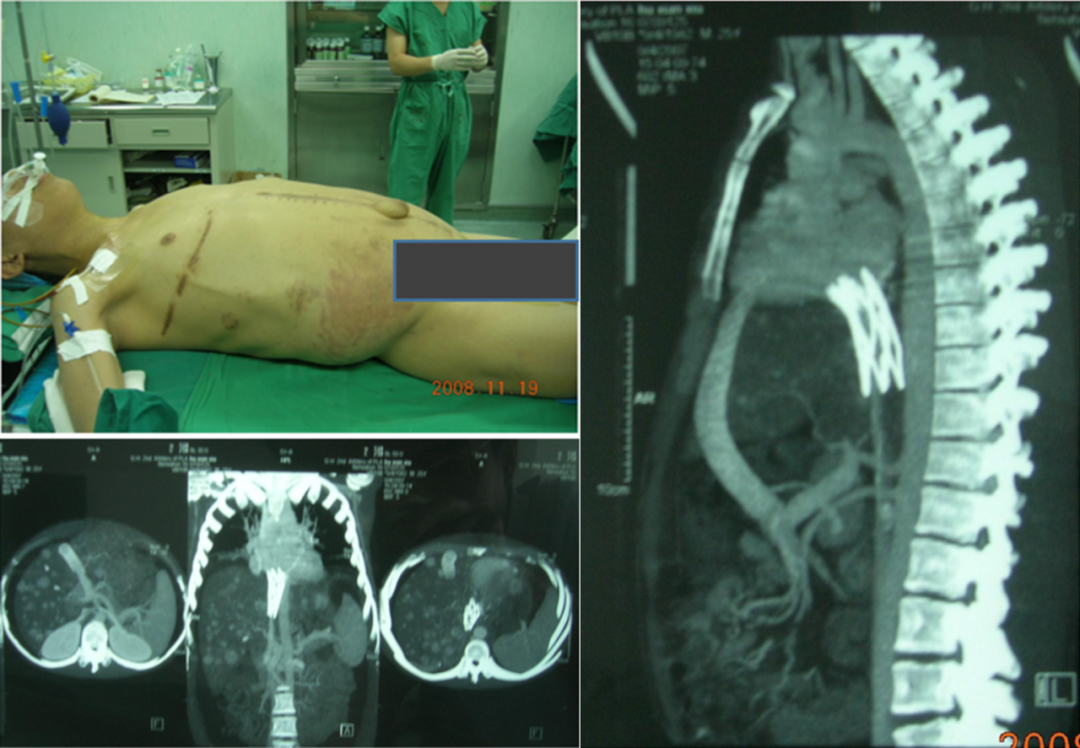

★ Case 4

术后多次复发-吻合口成形术

患者,男,28岁,因反复腹胀4年余于2008年7月3日入院:4年前,于当地医院行“下腔静脉支架植入术1个月后,在北京一家医院行肠房人工血管转流术,症状明显缓解。1年半以后,出现大量腹水,并发脐疝。超声示人工血管通畅。服用保肝、利尿药物无效,病情渐重,多次出现肝昏迷。为进一步治疗,来二炮总医院。当时测腹围110cm。

入院行腹膜腔-颈静脉转流泵植入术。腹水减少,腹围在85cm左右。

半年后,转流泵阻塞,腹水增多,再次入院。腹围105cm。

4个月期间,腹水回输43次,每次1000-3000ml.间断补充白蛋白。

白蛋白24.6g/L-----35.1g/L

血色素92g/L-------143g/L

腹围88cm---------92cm